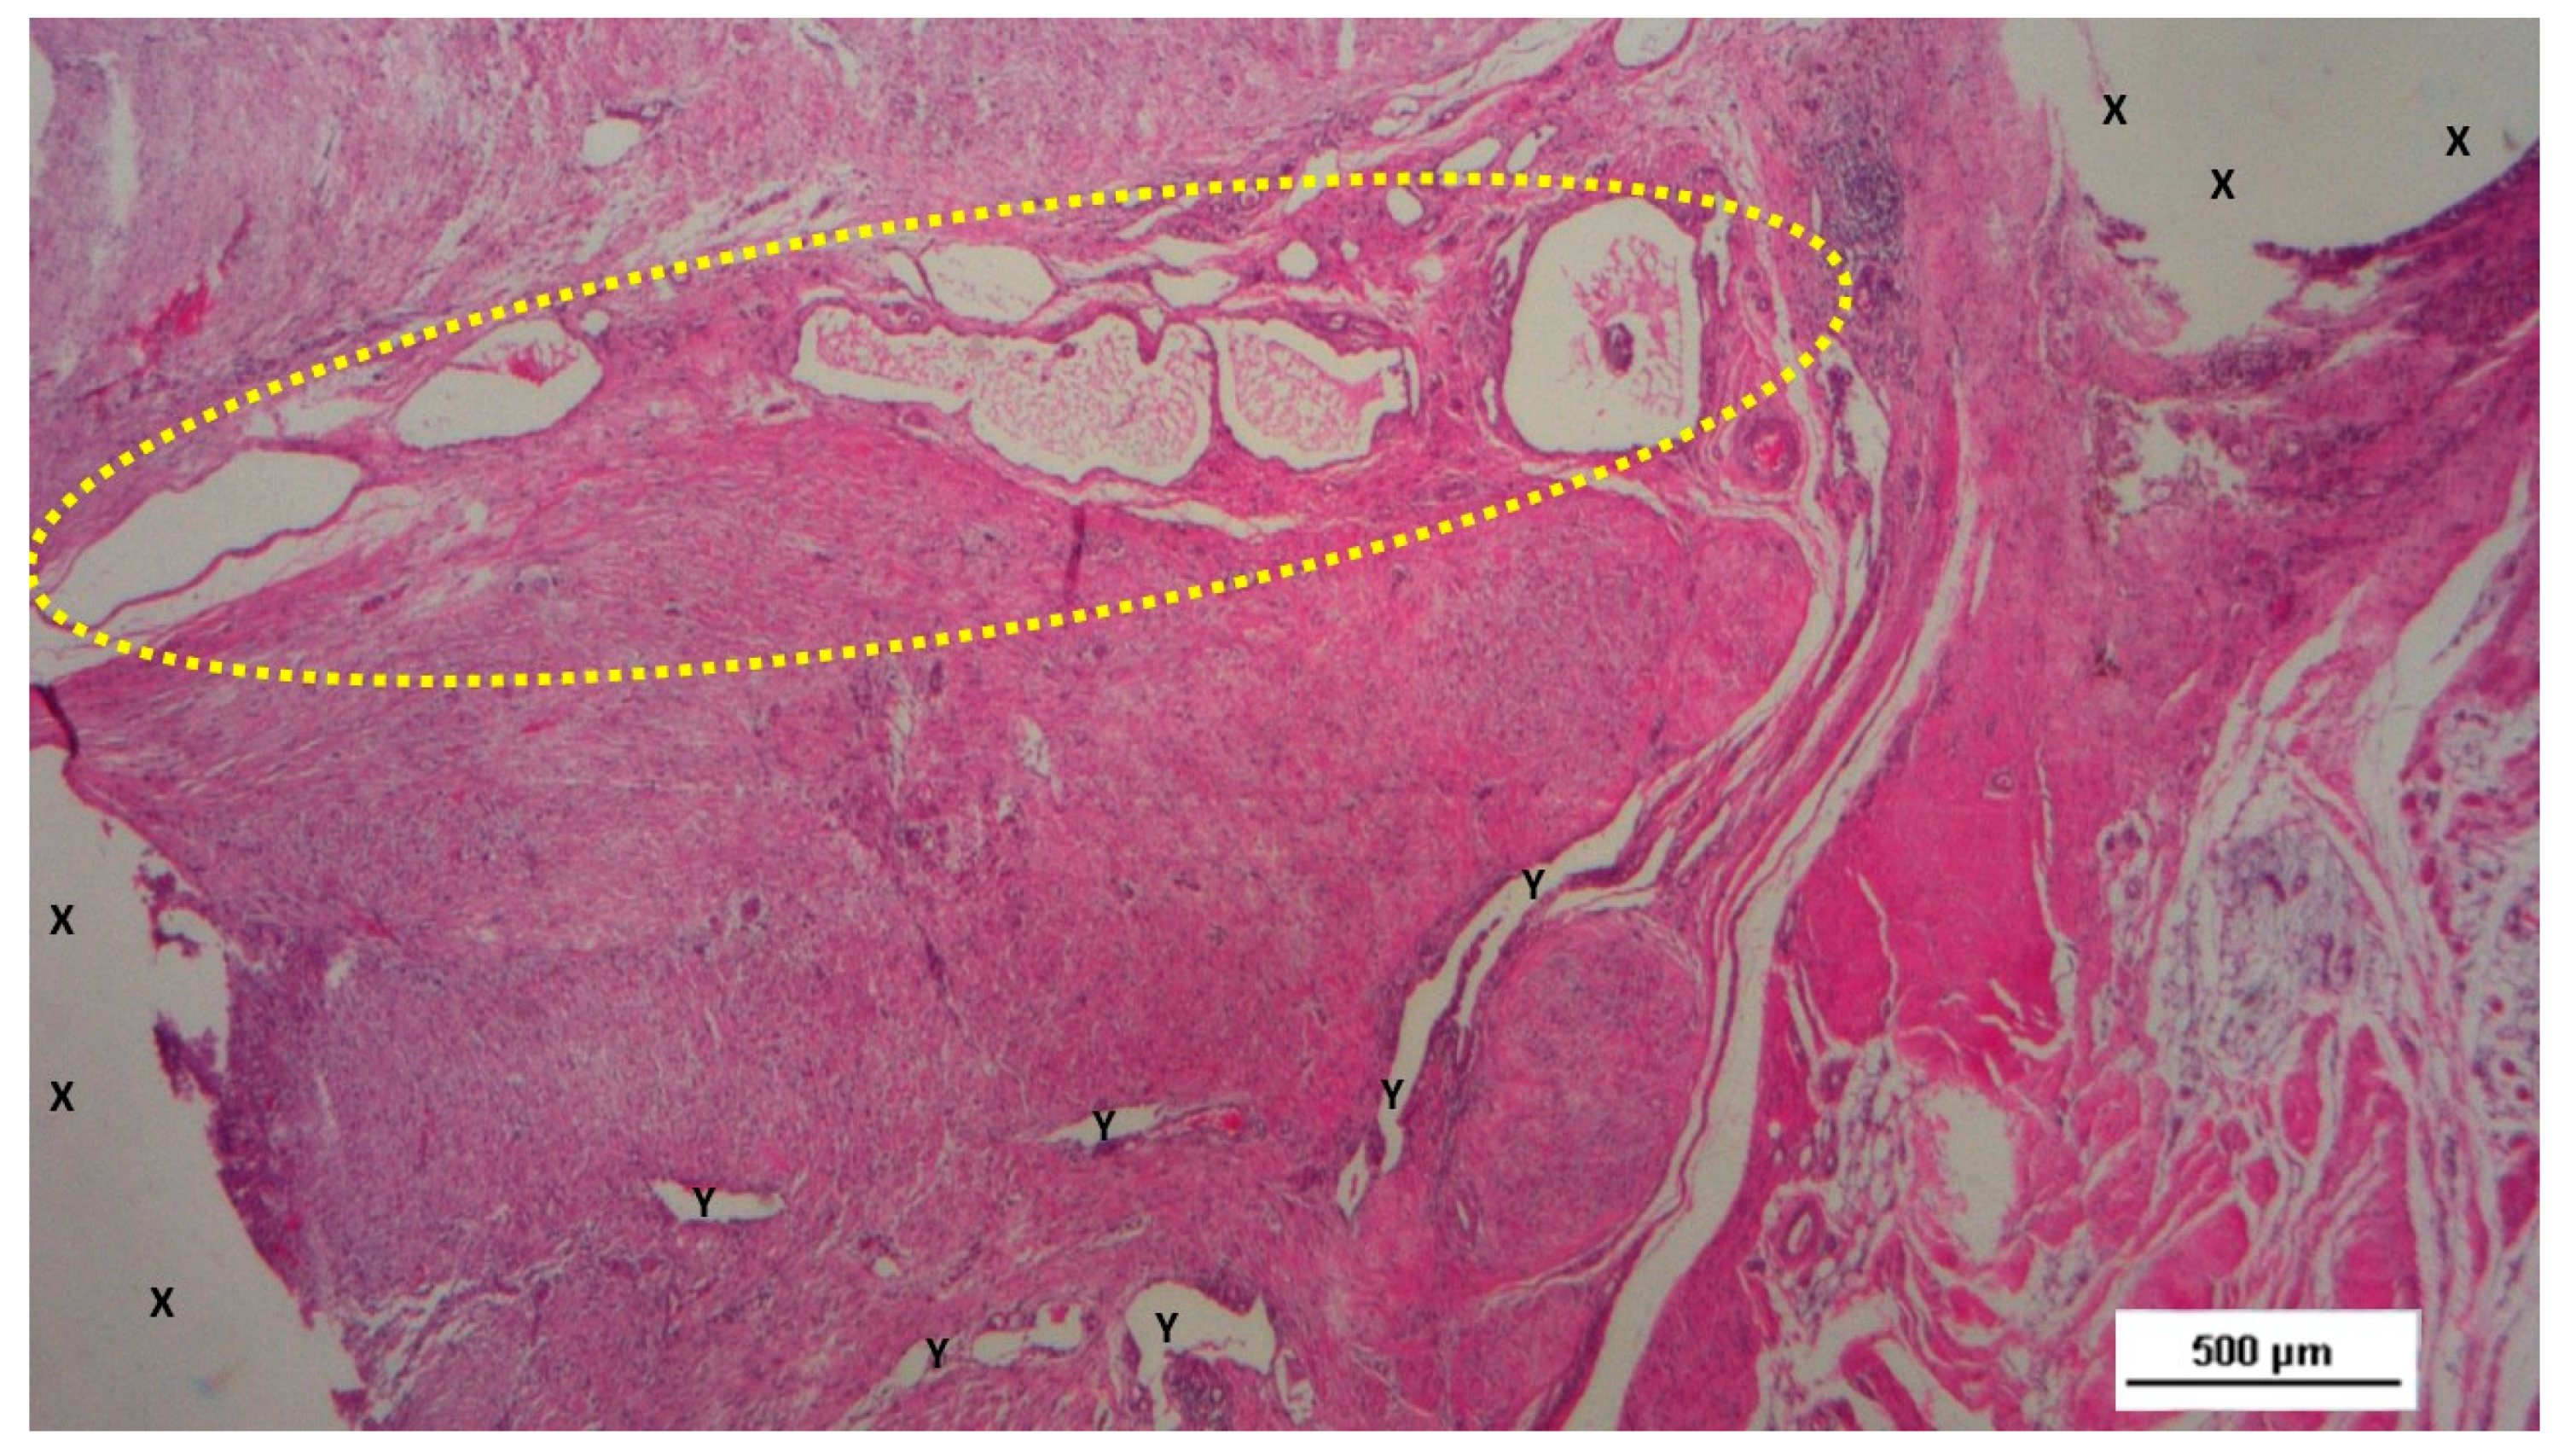

In the mid-term period (3-4 months post-implantation), H&E staining showed a significant presence of vascular structures within the S&S device. Notably, in this postoperative period no signs of inflammatory response against the fabric of the S&S device could be evidenced. The arterial structures displayed advanced development, with well-defined endothelial and muscular layers, while the adventitia was properly enveloping the vessels. Similarly, the veins exhibited noticeable structural maturation compared to the earlier period (Figure 7, Figure 8 & Figure 9).

Figure 7. Biopsy specimen excised three months post-surgery. Microphotograph reveals a large convoluted arterial structure (yellow circle) and several clusters of veins (Y) in advanced stages of development, embedded in well-perfused connective tissue near the S&S scaffold fabric (X), which is free from inflammation. The lower right corner highlights bundles of mature muscle elements (red spots). HE 25X.

Figure 8. Biopsy taken four months post-surgery from the 3D scaffold of the S&S Hernia System. Numerous clusters of vascular structures are in advanced stages of development (yellow circle), surrounded by well-hydrated, slack connective tissue containing several muscle bundles (red-stained dotted and striped structures) near the S&S fabric (X), with no signs of inflammation. HE 25X.

Figure 9. Biopsy taken four months post-surgery from the 3D scaffold of the S&S Hernia System. Numerous clusters of vascular structures are in advanced stages of development (yellow circle), surrounded by well-hydrated, slack connective tissue containing several muscle bundles (red-stained dotted and striped structures) near the S&S fabric (X), with no signs of inflammation. HE 25X.